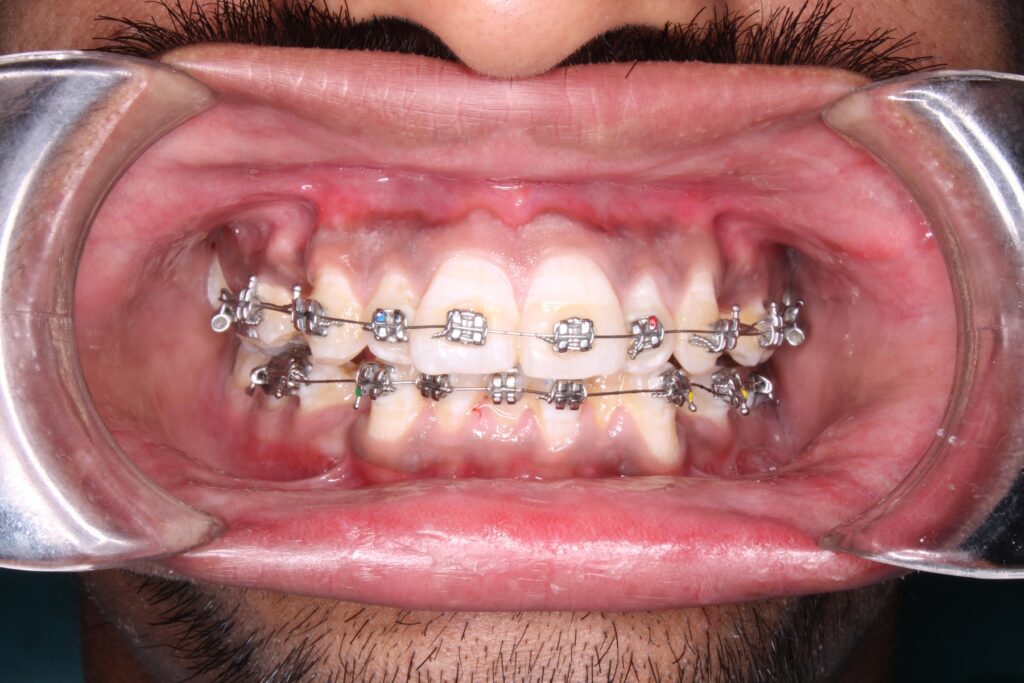

Benefits of Braces

Look what orthodontic treatment does to your teeth

From day one to a beautiful smile — time-lapse transformation!

What types of braces are available?

We offer different types of braces to suit your lifestyle and needs:

- Metal Braces: Strong and effective for all types of cases

- Ceramic Braces: Tooth-coloured, more discreet

- Self-Ligating Braces: Comfortable and easy to clean